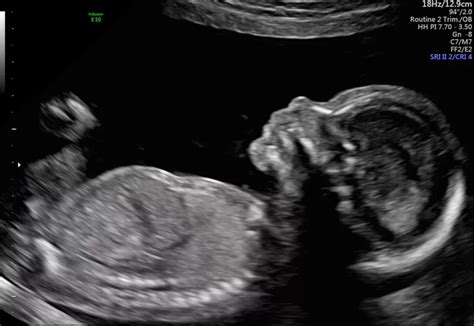

Hey everyone, let’s chat about something that can be a bit nerve-wracking: the 20-week scan, also known as the anomaly or morphology scan. It’s a super important check-up during pregnancy, where the sonographer takes a good, long look at your little one to make sure everything is developing as it should be. Now, sometimes, things don’t look quite as expected, and that’s where the idea of a ‘false positive’ can creep in. So, how common is a false positive at the 20-week scan NHS ? That’s a question many expectant parents grapple with, and it’s totally understandable why.

Understanding the 20-Week Anomaly Scan

Let’s dive a bit deeper into the 20-week anomaly scan , guys, because it’s a biggie in the prenatal journey. This isn’t just a quick peek; it’s a comprehensive examination aimed at spotting potential structural abnormalities in your developing baby. Think of it as a detailed architectural survey of your little one, from head to toe. The scan typically takes about 30 to 60 minutes, and it’s performed by a highly skilled sonographer. They’ll be looking at all the major organs – the brain, heart, lungs, kidneys, stomach, bladder – as well as the limbs, face, and the umbilical cord. They’ll also measure your baby’s growth and check the placenta and the amniotic fluid levels. It’s a truly amazing piece of technology that allows us to get such a detailed view inside the womb.